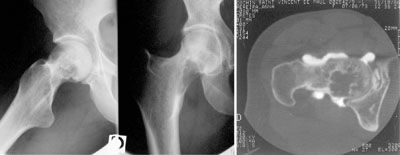

Pédagogie Conduite à tenir devant une tumeur à cellules géantes , Bernard Tomeno Hôpital Cochin, Paris, France N°136 - Août 2004 ● 16 min de lecture